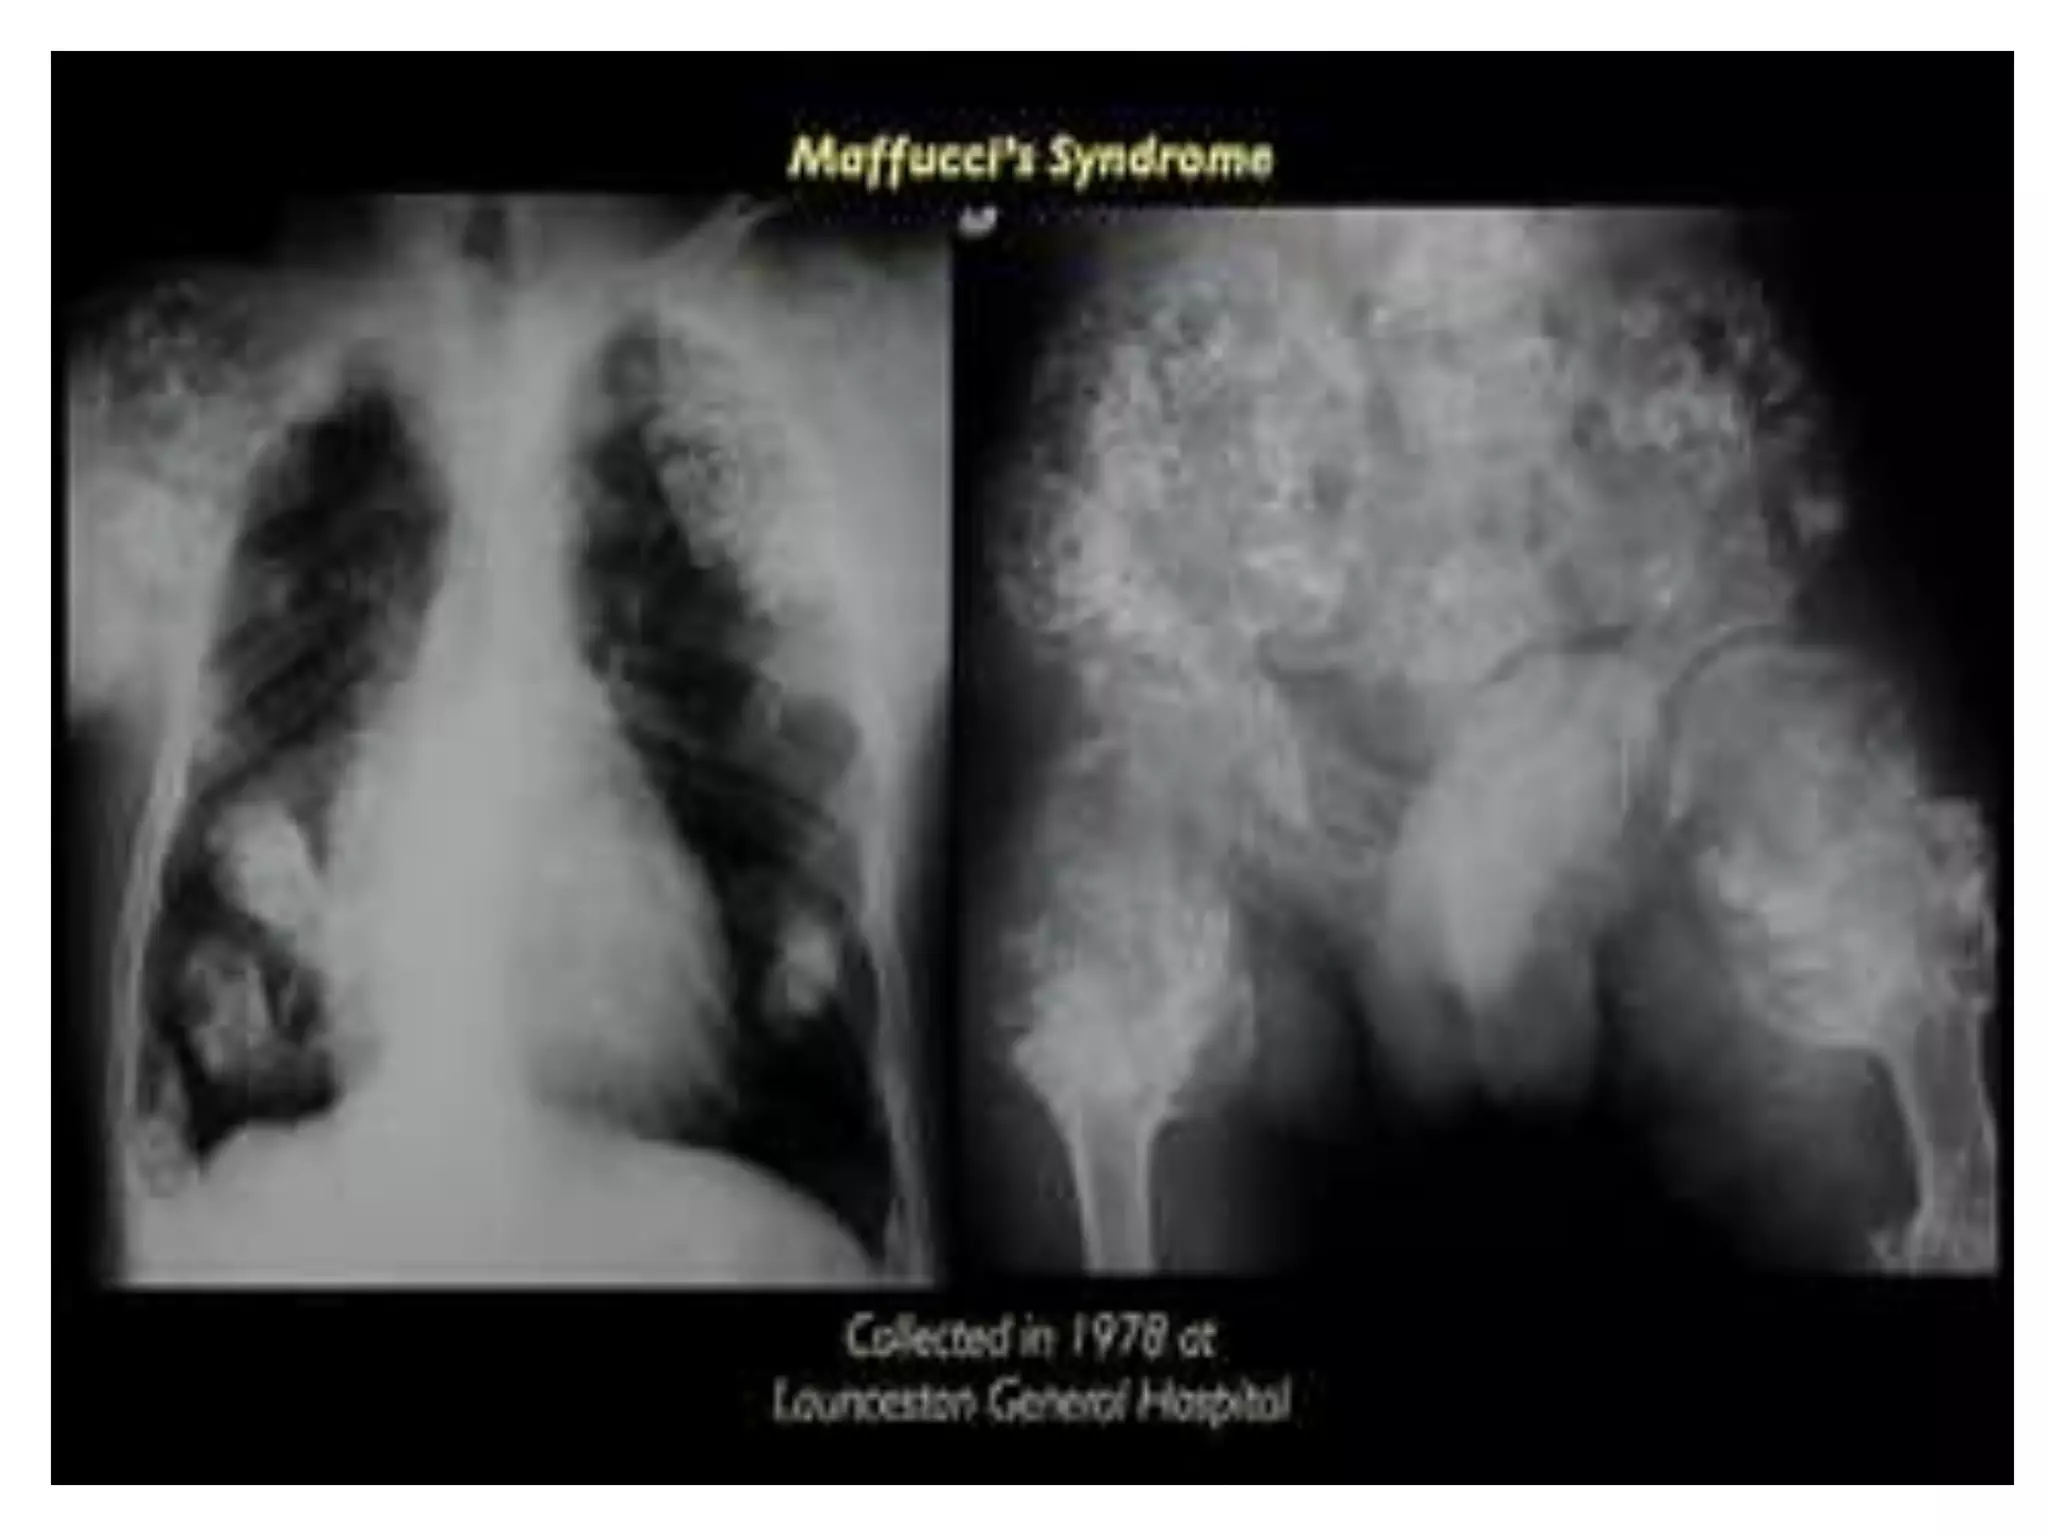

Mafucci’s syndrome(rare)

characterised by multiple

enchondromas.

Soft tissue

haemangiomas

(skin/viscera).

Malignant changes in

soft tissue and bone

lesions.

Mafucci’s syndrome(rare) characterised bymultiple enchondromas. Soft tissue haemangiomas (skin/viscera). Malignant changes in soft tissue and bone lesions.